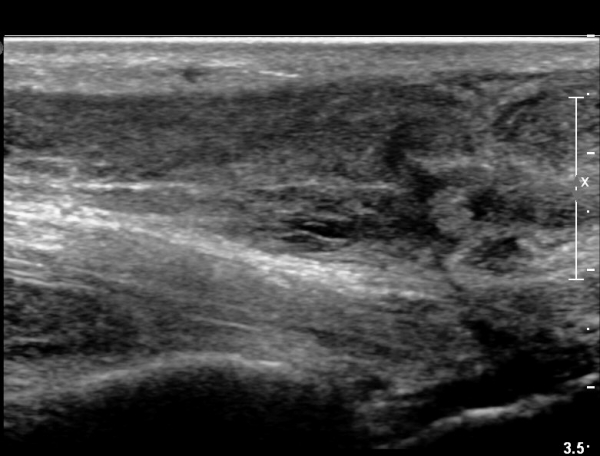

¾ÆÅ³·¹½º°Ç Àú¿¡ÄÚºÎÁ¾ÀÌ °¨¼ÒµÇ°í  ÆÄ¿­ºÎÀ§ Àú¿¡ÄÚ°¡ È£ÀüµÇ¾î

°ÇÀÇ ¼¶À¯¼º¾ç»ó(fibrillar pattern)ÀÌ È¸º¹µÇ°í ±¹¼ÒÀû ¿¬°á¼º ¼Ò½ÇÀÌ »ç¶óÁü(»çÁø 9, 10, 11, 12).